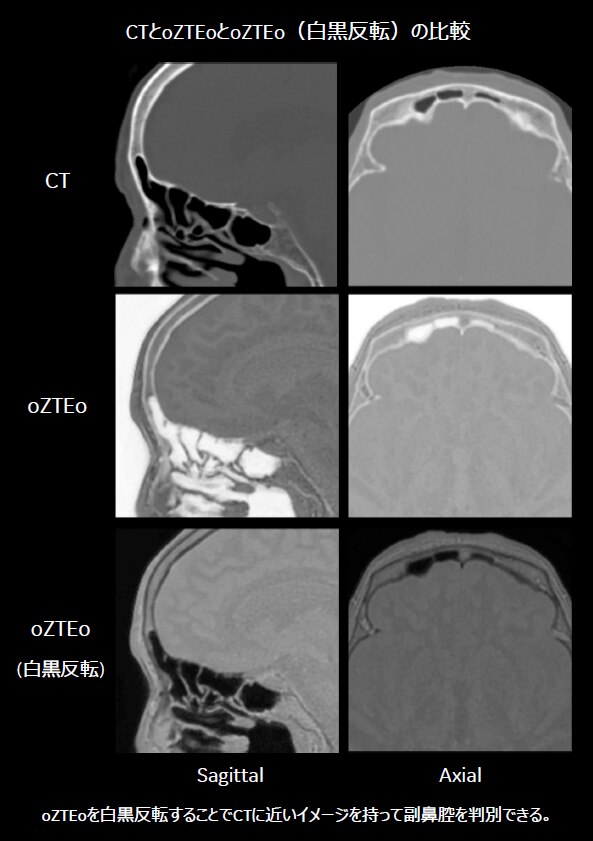

従来は、造影剤を用いたCT検査にて、骨、動脈、静脈を3D画像化し術前シミュレーション用として提供している。また、当院では術中感染リスクの観点より、副鼻腔、特に前頭洞の画像化も同時に行っている。oZTEoのが使用可能になったことにより、MRIのみにて骨(oZTEo)、動脈(3D-TOF)、静脈(3D-PC)の作成が可能となった。また副鼻腔の描出に関しては、CTと比較してもその描出能に問題はなく、比較的容易にVR作成可能であることが分かった。これらのことから、追加の撮像時間(3シーケンス撮像のため)を要するが、造影剤が不要であるという利点を活かしたMRI術前シミュレーション用フュージョン画像の提供が可能となる。

oZTEoの画像から骨、副鼻腔を、MRA(3D-TOF)から動脈を、MRV(3D-PC)から静脈をそれぞれVRを作成しフュージョン処理を行った。エントリーポイント(開頭野)決定のために、静脈と前頭洞(副鼻腔を含む)の位置確認が重要となる。そのため、骨、副鼻腔、静脈を同時に表示する必要があり、その画像情報は左右のどちらからアプローチするかの決定に用いられる。

脳神経外科医からは、MRIで作成した画像でもCT同様に前頭洞を確認でき、また造影剤を使用しなくても上矢状静脈洞や架橋静脈等の静脈や動脈の確認も可能であるため、術前シミュレーション画像として有用である、とコメントをもらっている。最大の利点としては、造影剤を用いることなく被曝無しでの術前情報取得が可能という点であり、患者負担を軽減することが期待できる。